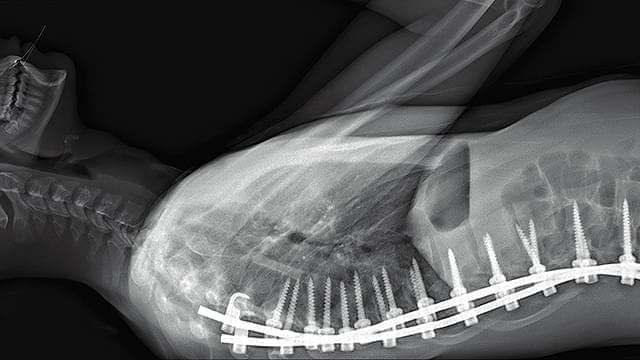

本作は「人体」が最大の関心事となる場所=パリ北部近郊の5つの病院のオペ室を舞台に展開する “21世紀の人体解剖書”。医師視点のカメラや内視鏡の映像を使い、脳や大腸、眼球、男性器など様々な外科手術や帝王切開の模様を医師の視点で見つめる。思わず目をそむけたくなるほどの生々しさと同時に、肉体が持つ生命力や美しさを感じさせてくれる。また、死と隣り合わせの職場での医療従事者たちの心境や、死体安置所でのおくりびと達の仕事ぶりが描かれ、医療とは何か? 肉体と魂とは何か? 人体の神秘と人間の恐怖の根源を探るドキュメンタリーだ。

このほど公開された約100秒の本予告編は、「刺激が強いと感じられる映像が含まれています」という警告文からはじまる。登場するのは現代の病院で行われている様々な外科手術の現場。普段はなかなか目にすることのできないオペの様子は「いったい何をしているのか?」と気になる映像が満載だ。また、本作には医療従事者たちの本音のやりとりも数多く収められており、「集中治療室で働いていると、(毎日死と向き合うから)“今を大事に”と思うの」という看護婦たちの切実な会話から、「週に100人治療し、20人手術している。まるでロボットだ」とこぼす医師の独白も捉えられ、現在の深刻な医師不足の問題も提起する。